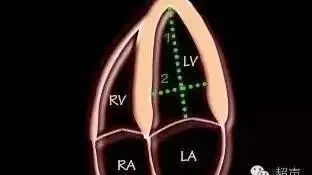

术前超声检查—心动超声

左室前后径

左室上下径、左右径

CT重建分析:

左室前后径:31mm 左室上下径:60.8mm 左室左右径:37mm